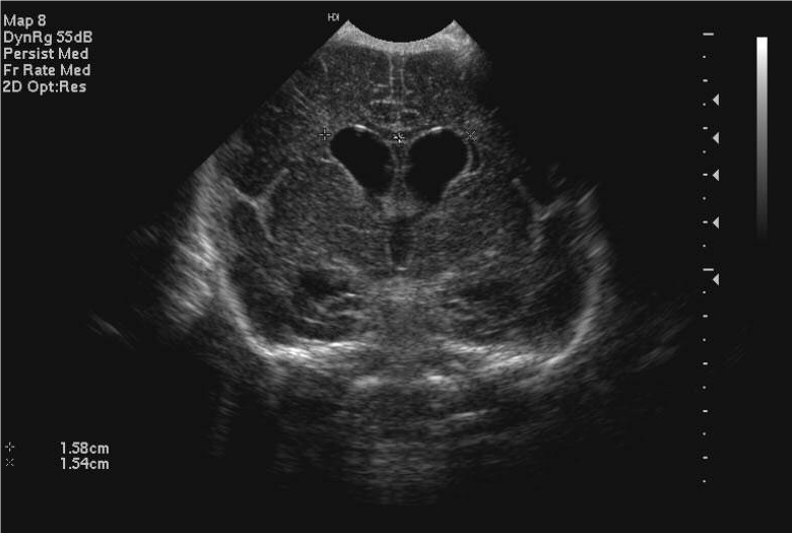

- When there is ventricular dilatation on scan, the ventricular index is measured to given an objective comparison between scans

- The ventricular index is the distance from the midline to the most lateral part of the lateral ventricle on a coronal scan taken at the level of the foramina of Munro

- The chart below gives the 3rd, 50th and 97th centiles for ventricular index by gestation